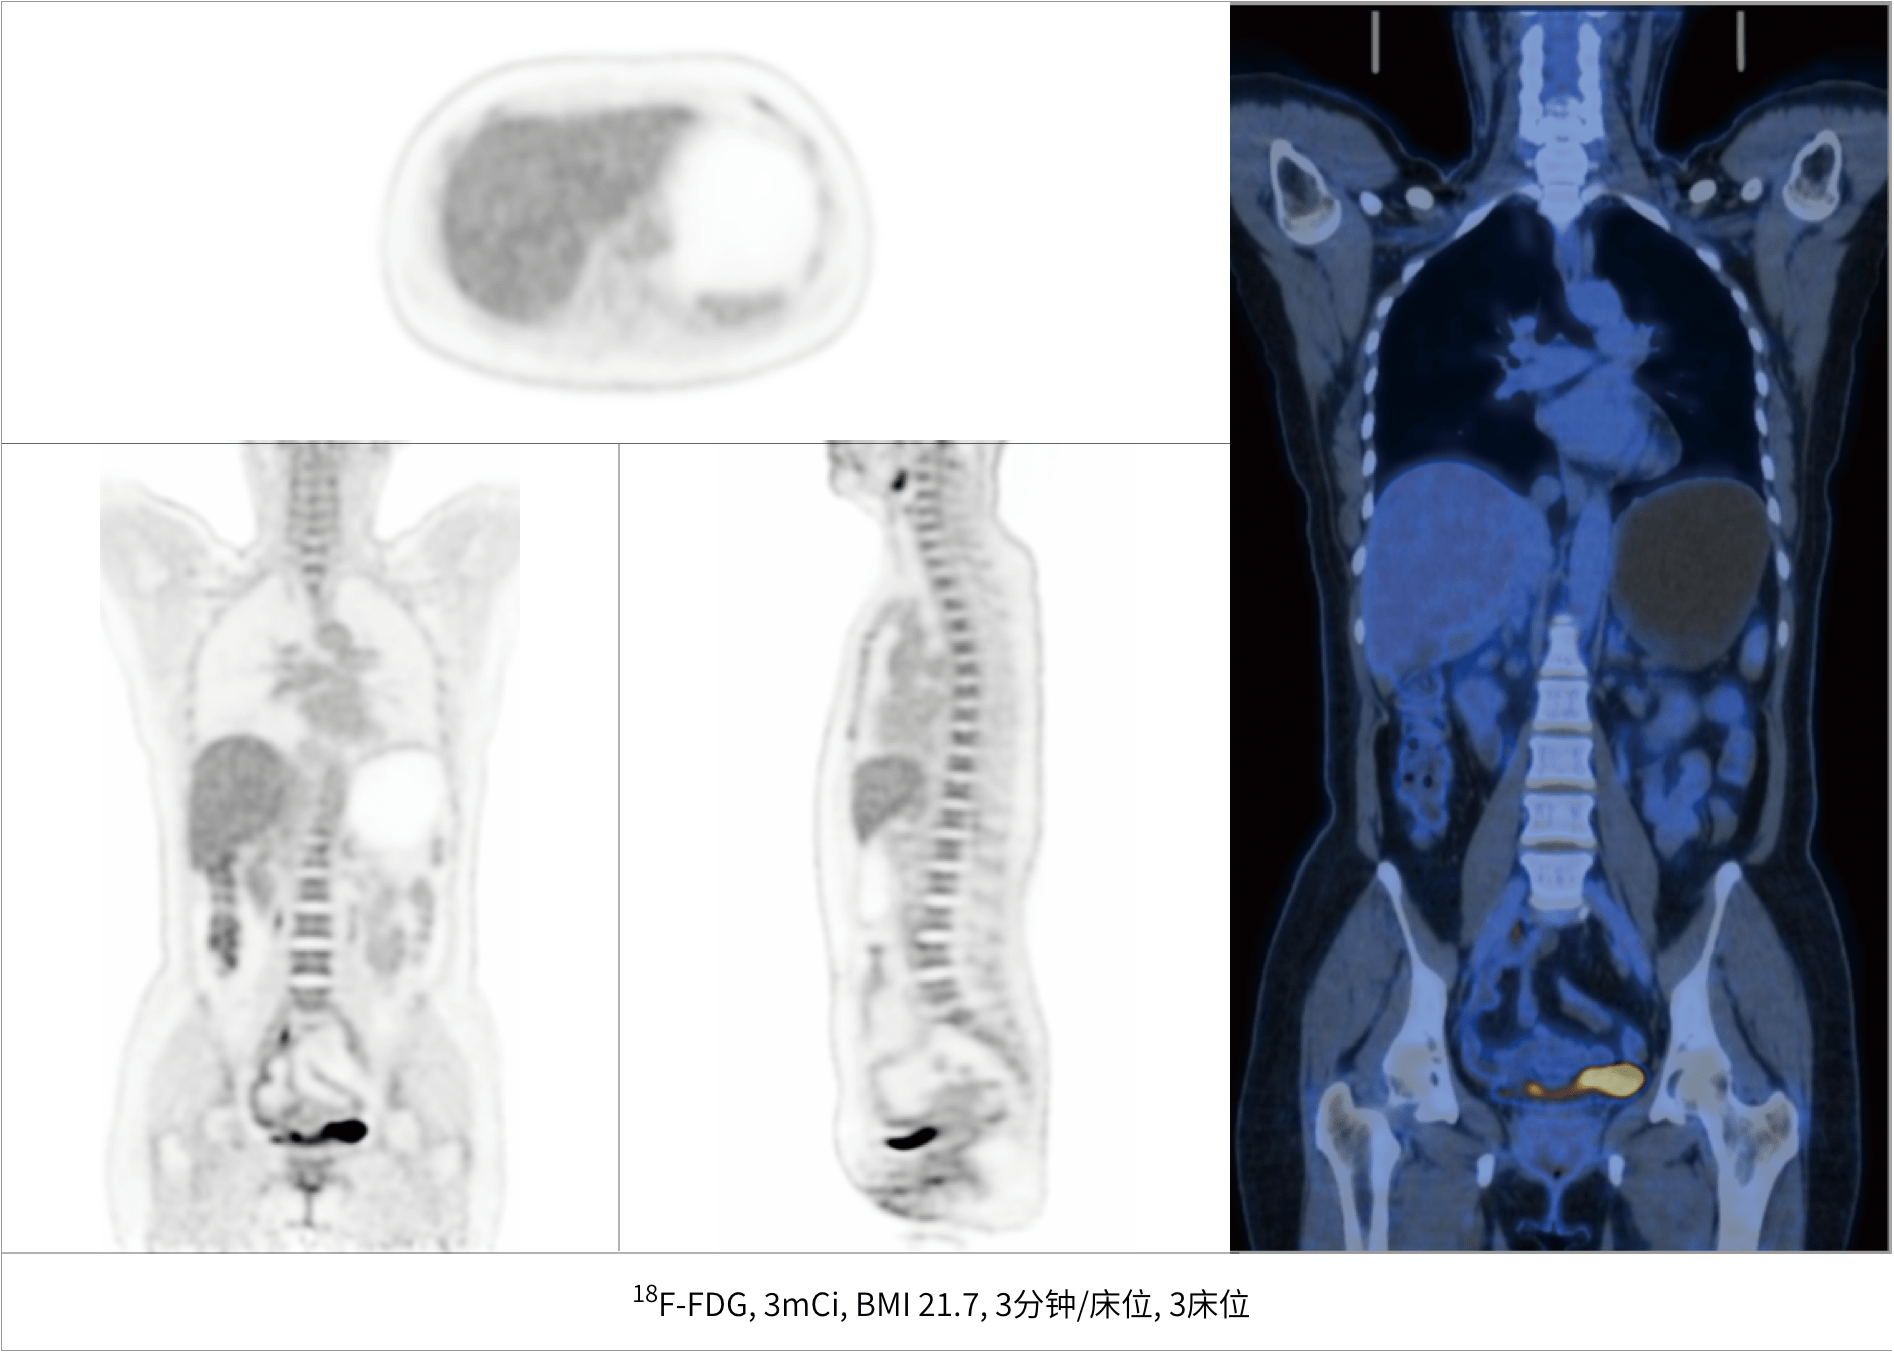

超清显像

TOF + PSF

微小病灶无以遁形